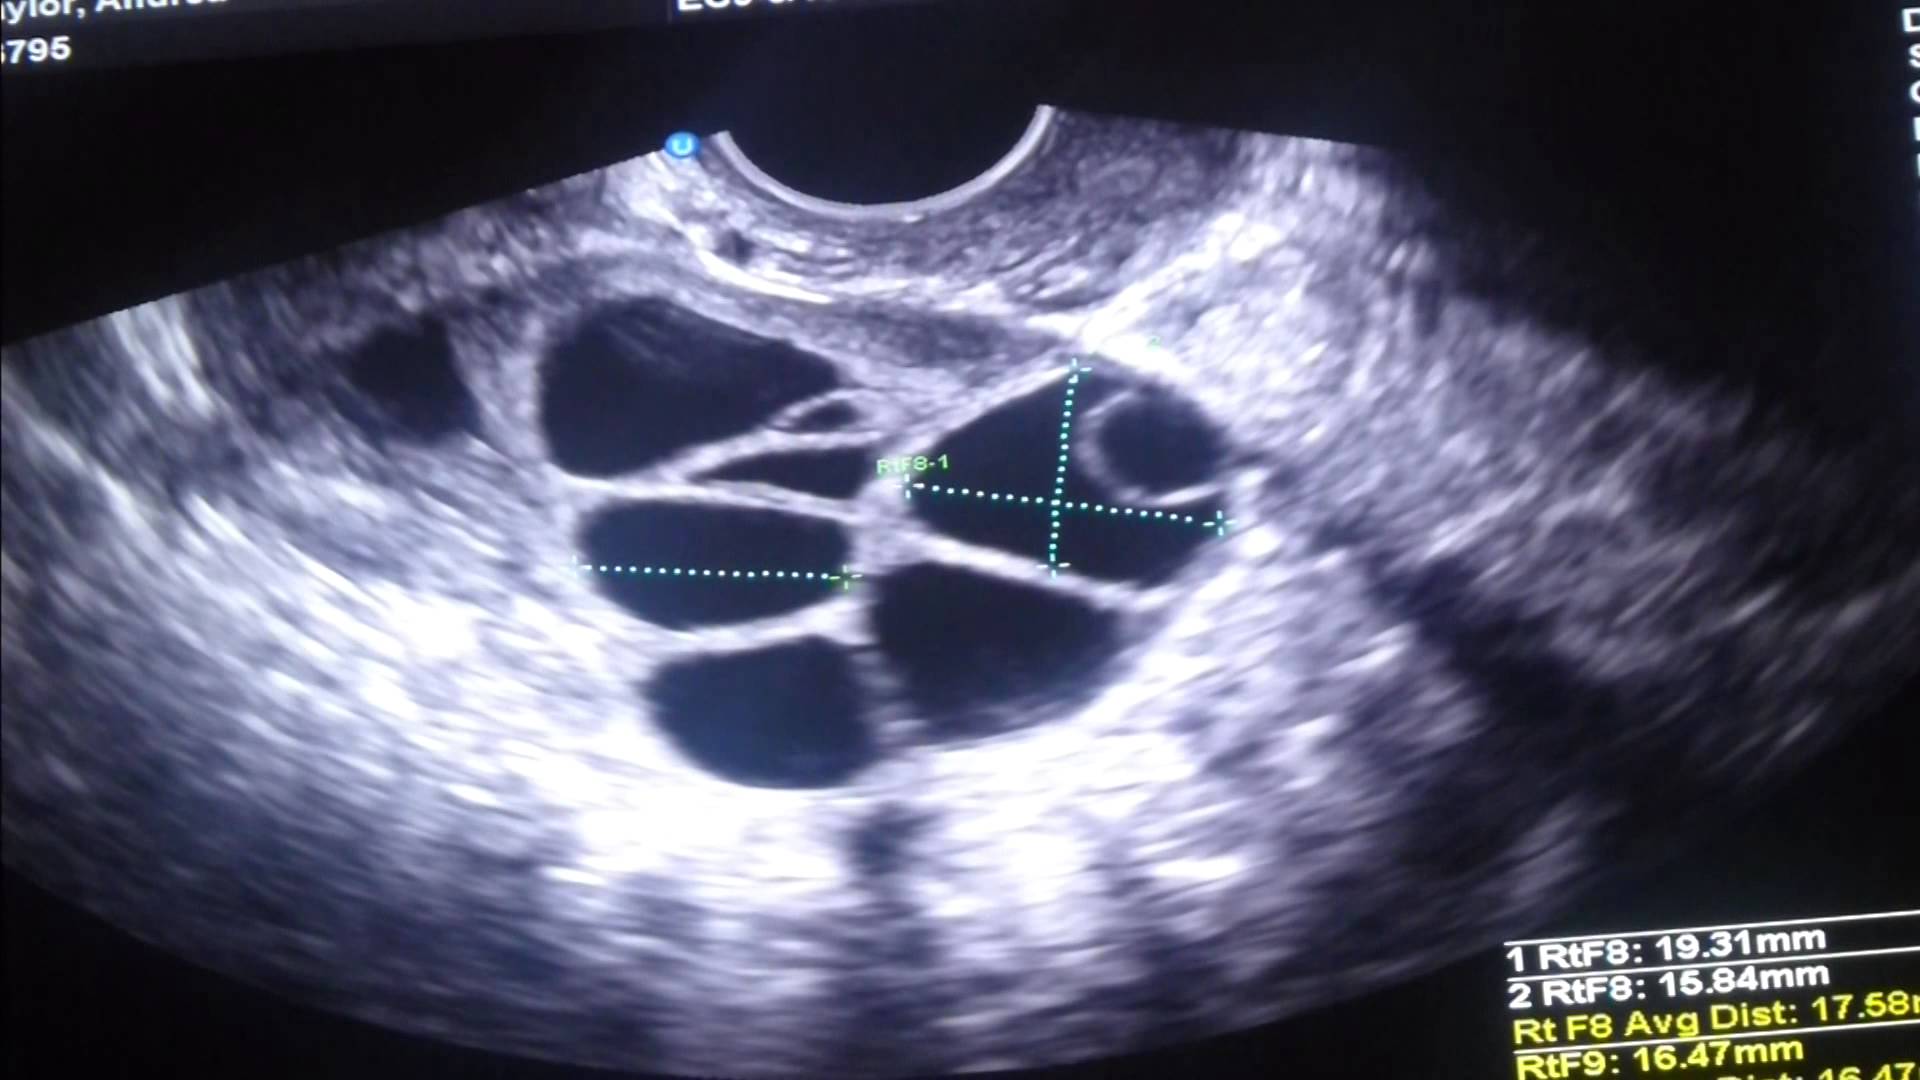

Прогрес се наблюдава и в ултразвуковата визуализация и използването на лека упокойка по време на пункцията, при която се извличат яйцеклетките от яйчниците. Преди се е използвал по-инвазивен лапароскопски метод.

Фоликули под ултразвук